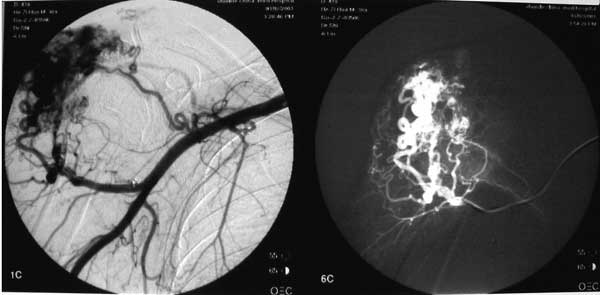

经右侧股动脉穿刺,将导管通过腹主动脉、胸主动脉、无名动脉超选入右侧锁骨下动脉,造影示肩部软组织大量动脉血管丛存在,主要供血分支由胸肩峰动脉和旋肱后动脉提供。

以超选择进入供血分支,并将其采用海绵、钢圈闭塞,造影证实血管瘤供血动脉完全阻断。